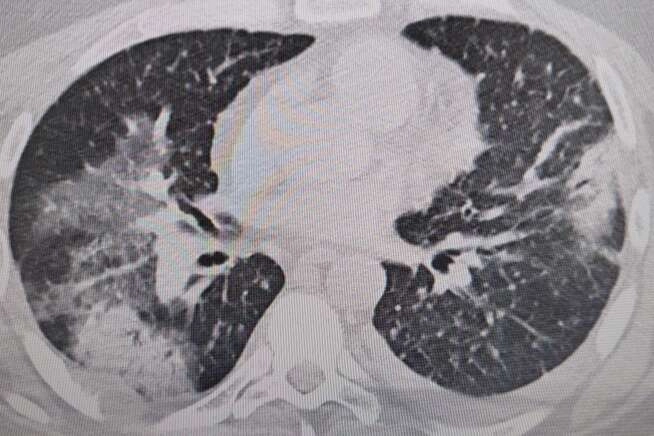

‘Legionella" adı verilen bakteri neden oluyor.Prof. Dr. Şevket Özkaya, “Legionella” bakterisinin klima sularında üremesiyle insanların yaz zatürresine yakalandıklarını ve kış aylarına göre çok daha fazla vakayla karşılaştıkları bilgisini verdi. Klima zatürresinin özellikle kronik rahatsızlığı olanlarda ölümcül olabileceğini belirten Prof. Dr. Şevket Özkaya önemli uyarılarda bulundu. Özkaya, “Klimaların havalandırılmasıyla beraber insanlar 'lejyoner' bakterilerini akciğerlerine aldığında 'klima pnömonisi' ya da 'yaz zatürresi' dediğimiz hastalığa yakalanıyorlar. Bunun özellikle kronik astım, KOAH ve kanser hastalarında ölümcül sonuçlar doğurabileceğini biliyoruz” dedi.

Özellikle klimaların iyi temizlenmesi gerektiğini ifade eden Prof. Dr. Özkaya, “Klima zatürresinde grip gibi belirgin değil. Eklem ağrıları, ateş, halsizlik, ishal gibi hafif soğuk algınlığı belirtileriyle seyrettiği için de hemen anlaşılmayabilir. Özellikle kronik hastalığı olanlarda hayati sonuçlar doğurabilir. Ani ısı değişiklerine, örneğin sıcaktan soğuya ve klimalara maruz kalmakla oluşan belirtiler korona ile de karışabilir. Vatandaşlarımız, özellikle kapalı yerlerde kendilerine dikkat etsinler. Klima ayarlarını 22 derecenin altına düşürmesinler. Özellikle de bu ısı değişimlerine uzun süre maruz kalmamalarını öneriyorum” şeklinde konuştu.